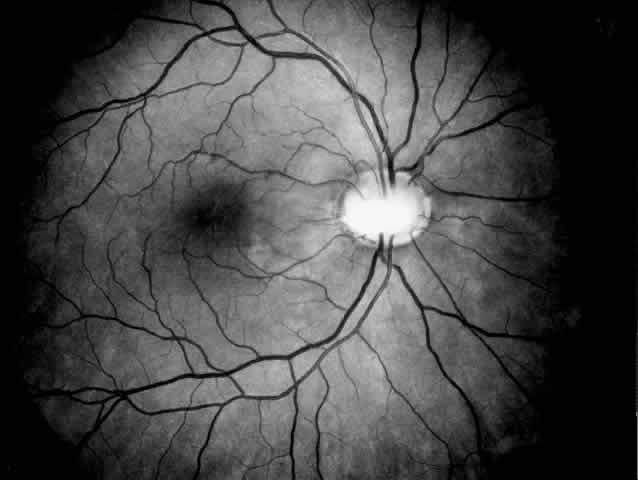

PAPILLORENAL SYNDROME. The papillorenal syndrome has been defined by Bron18 as a dominantly inherited disorder with a bilateral dysplasia of the optic discs associated with a severe form of glomerulonephritis that may lead to renal failure. The disc anomaly ranges from morning glory anomaly or the Handmann anomaly to coloboma or optic pit (Fig. 2). Optic nerve function may be impaired, and in addition there is a risk of visual loss as a result of serous macular detachment. The pathogenesis of the renal changes and the genetic mechanism linking the renal and ocular abnormalities are unknown.

Fig. 2. Papillorenal syndrome with the Handmann optic disc anomaly and macular changes as a result of chronic macular detachment in a renal transplant patient. An optic pit and severe hypertensive changes were observed in his brother, who also received a renal transplant (see Fig. 1). Poor renal function had been recorded in six other family members in three generations.